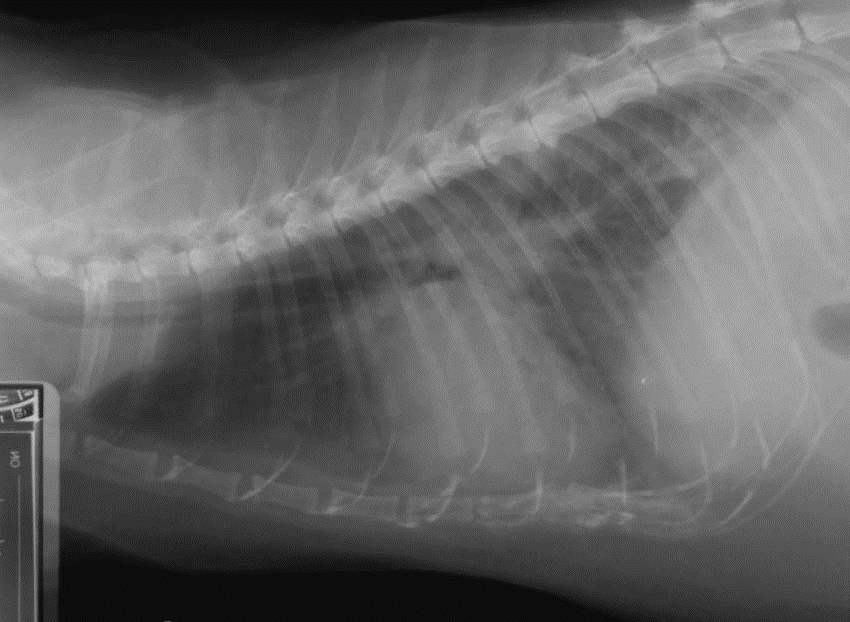

What can be seen?

Increased opacity in dorsal caudal lung fields – interstitial pattern.

Potential vascular pattern in pulmonary vessels?

Heart height around 2/3 of thorax so fine, width slightly enlarged? Over 2 rib spaces. But axial rotation- so accurate?